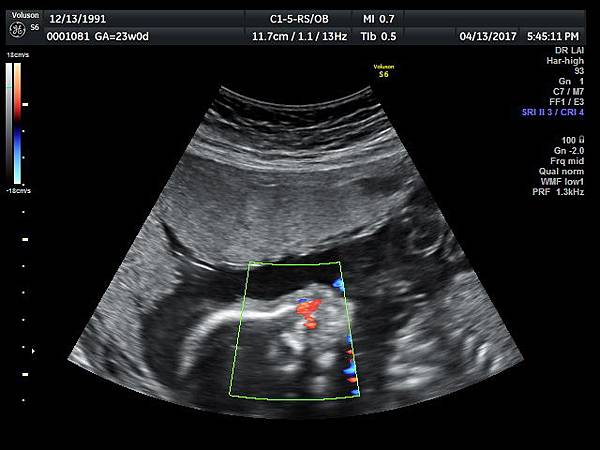

孕兒診所備忘錄 230 cleft lip and palate - II with normal heart

cleft lip and palate - II with normal heart